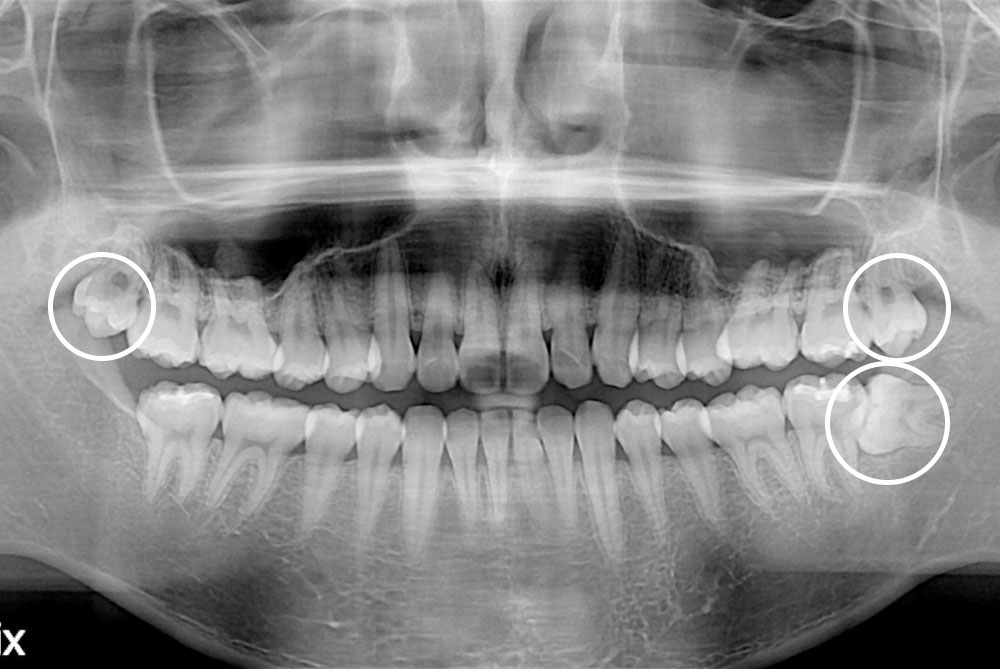

[사랑니] 매복 사랑니 발치

치료전 : 2020-06-03

세종치과는 구강악안면외과학 박사이신 원장님이 발치하는 치과입니다.